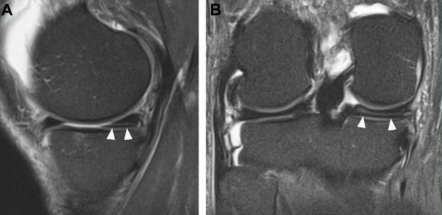

X线只能看见骨头,而MRI能清晰显示半月板、韧带、软骨和关节液,是诊断半月板损伤的首选检查。

·撕裂类型:纵裂、水平裂、桶柄样撕裂等;

·损伤部位:内侧或外侧半月板,前角、中段或后角;

尤其在3T磁共振高分辨序列下,医生能像读“地图”一样精确定位裂口,为手术修复或保守治疗提供方向。